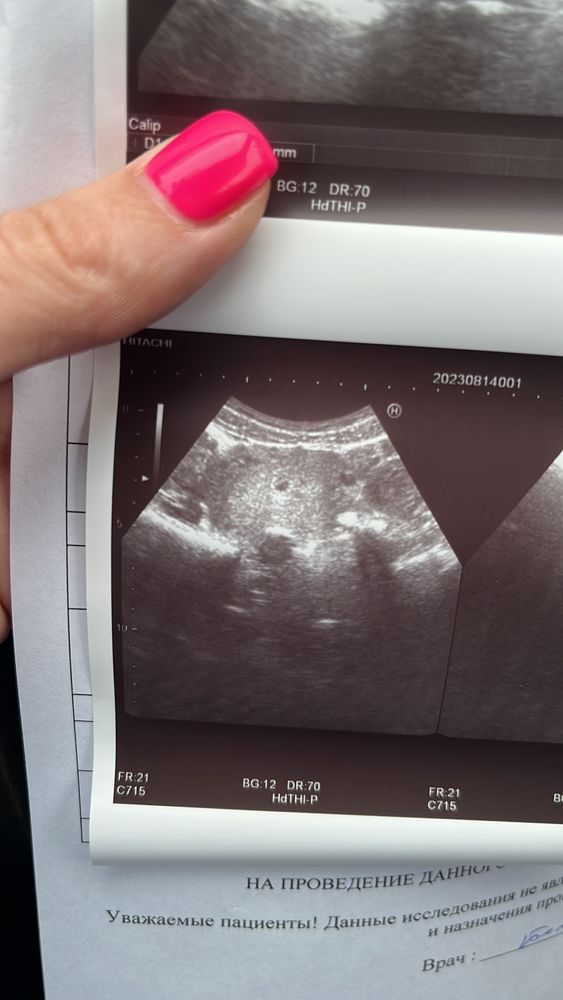

Вопросы о беременных и для беременных двойнейДевочки, Ходила сегодня на узи, врач сначала принимать не хотел потому, что задержка не большая, хотя у меня хгч уже больше 1500, потом еле нашел ПЯ размером 5-6 мм, но я на узи вижу еще одну точку

возможно, что это второе ПЯ? Или это ЖТ?

Но по снимку УЗИ вы ничего не скажете, точно так же и срез сосудов выглядит и скопление эндометрия небольшое и полип и тд и тп. Это может только врач, делающий узи оценивать.